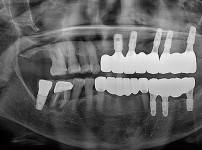

임플란트-전후사진4

치과를-선택할-때-꼭-확인하세요-서울숙면치과-임플란트-전후사진